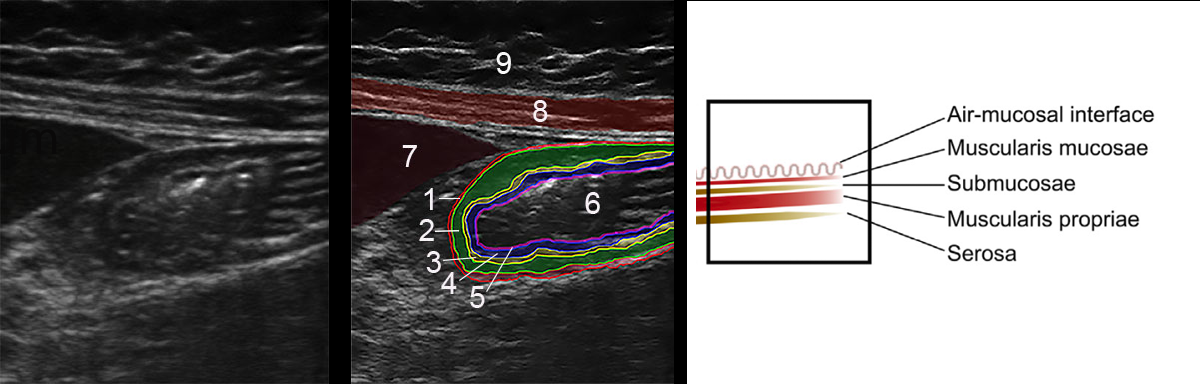

- The focused questions:

- Is the stomach empty or full ?

- If clear fluid is present in the stomach – calculating the volumen in the stomach

- Does the content in the stomach represent a risk for the patient ?